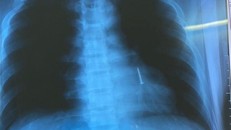

(Ngày Nay) - Tối 28/2, các bác sĩ khoa Nội hô hấp - Miễn dịch dị ứng, Bệnh viện Đà Nẵng đã nội soi gắp thành công cây đinh sắt dài 3cm nằm trong phế quản cho một bệnh nhân làm nghề thợ hồ.